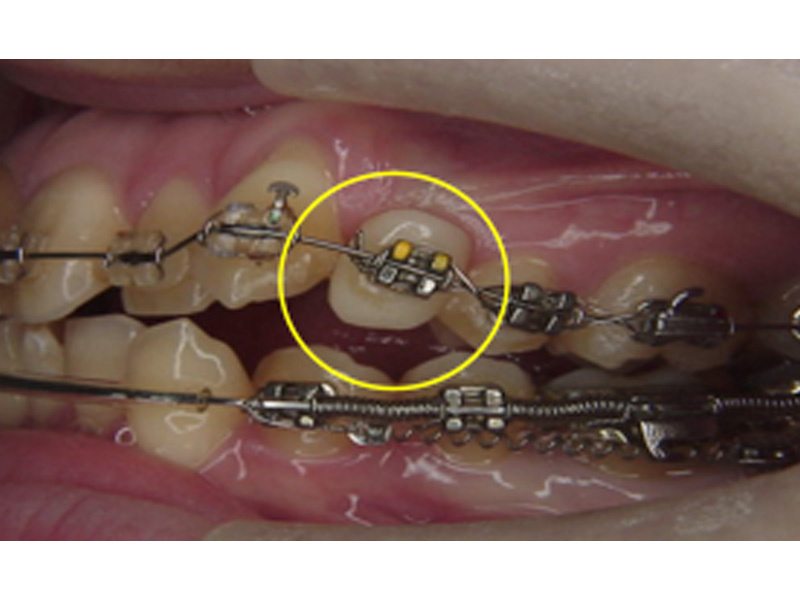

ダミー歯

歯の突出やデコボコの程度が大きい場合、歯を抜いて矯正治療をすることがあります。箇所によっては、その隙間が見た目に気になると感じることがあるかもしれません。

そのような場合、その部分の矯正装置に人工歯を組み込むことができます。飾りなので、咬むのに使うのは厳禁ですが、見た目は十分にカバーされます。唇側・舌側のいずれでも、可能です。